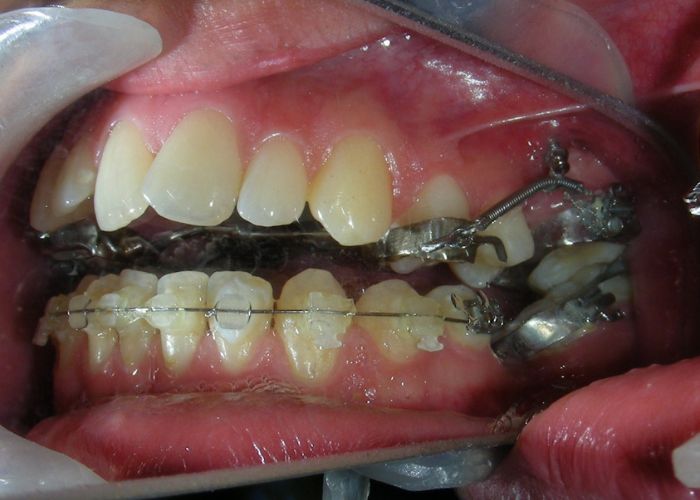

The vertical vector of intrusion was located too far posteriorly to allow for the placement of TADs in that region. At this point, the utility arch developed by Dr. Ricketts was introduced into the mechanics . I referred to as the “Tilting Utility Arch.” made with Blue Elgiloy .017″ × .025″. It was employed as a lever arm to transmit the intrusive force generated by the coil spring and anchored by the TADs.

The upper brackets were bonded solely for the purpose of providing stability to the utility arch . Following the hierarchically structured treatment plan, we proceed with the alignment and leveling phase in order to enable mesialization of the posterior segments using sliding mechanics, which works effectively in conjunction with Roth prescription brackets .022.

- .018″ × .018″ Blue Elgiloy sectional archwire was placed in three segments in the maxillary arch to maximize the effectiveness of Class II intermaxillary elastics, in conjunction with space closure (mesialization) in the mandibular arch.

- 017″ × .025″ Blue Elgiloy sectional leveling archwire beetwen # 35-37 and 45-47

- 017″ × .025″ Stainless Steel (SS) + Closed-coil NiTi springs were activated between the molars and anterior segment

- 019″ × .025″ Stainless Steel (SS)

After two years of treatment using appropriate biomechanics, the overbite was successfully corrected from -8 mm to +1 mm, achieving complete closure of the anterior open bite without exacerbating the patient’s lower facial third vertical proportions. At this stage, occlusal contacts were verified using articulating paper, and functional movements of the canines and incisors were evaluated to ensure proper anterior guidance and disclusion patterns. The patient was then referred to speech therapy (myofunctional evaluation) as part of the pre-debond assessment protocol.